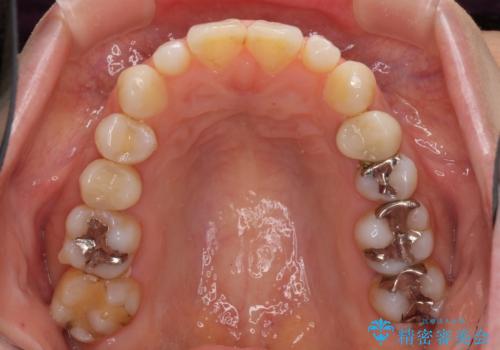

- 前歯のデコボコと矮小歯、更には痛みを感じる奥歯のむし歯を気にして来院された患者様です。

奥歯には根管治療が必要な歯があり、上顎側切歯は左右ともに矮小歯でした。

上下前歯のデコボコはワイヤーでもインビザラインでも対応可能でしたが、補綴治療が多く必要となることから、インビザラインでの矯正治療を行いながら、並行して補綴治療を行うこととしました。

まずは根管治療を行った上で矯正治療用の仮歯を装着し、矯正治療後半に補綴治療を並行して行うこととしました。